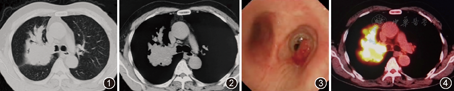

患者男,60岁。主因"间断咳嗽、喘息1年,伴痰中带血1个月"于2015年12月20日入院。患者1年前无明显诱因出现咳嗽,咳少量白痰,伴喘息,未予重视。后喘息间断发作,可自闻及喘鸣音,活动后明显。近1个月来出现痰中带血,伴纳差、乏力,体重下降。行胸部CT示右肺上叶团块状高密度影,边缘不规整,局部呈"指套征"(图1,图2)。既往吸烟指数800年支,未戒烟。体检:浅表淋巴结未触及肿大,右上肺呼吸音减低,未闻及干、湿性啰音。心腹未见异常。入院初步诊断:肺部阴影原因待查,肺癌?变应性支气管肺曲霉病?

住院后查血常规正常,嗜酸粒细胞计数正常。血清总免疫球蛋白E(IgE)和曲霉特异性免疫球蛋白E均正常。血癌胚抗原84.56 μg/L(正常参考值:0~5 μg/L)、鳞状细胞癌抗原1.8 μg/L(正常参考值:<1.5 μg/L)。痰找结核菌和真菌结果均阴性。1,3–β–D–葡聚糖和曲霉半乳甘露聚糖抗原均正常。支气管镜示右主支气管外侧壁可见息肉样新生物生长(图3)。给予右主支气管新生物行活检,病理示肺鳞癌。全身PET–CT显示右肺上叶不规则肿块影,代谢异常活跃,考虑恶性,伴右侧肺内多发转移,右侧肺门、纵隔多发淋巴结以及胰腺转移(图4)。最终诊断:肺鳞癌,Ⅳ期,T3N2M1。

本病例的肺部影像表现主要有以下特点:(1)右侧肺门处可见巨大肿块影;(2)肿块主要沿支气管走行,近肺门侧粗大,远端细小,呈"指套征",与右上叶前段和亚段的支气管形状相一致;(3)右上叶支气管管腔完全闭塞,并可见结节状新生物突入右主支气管;(4)纵隔窗平扫显示整个病灶密度欠均匀,局部可见少许点状钙化,而且"指套"近端呈软组织密度影,远端为低于软组织密度黏液嵌塞密度影,PET/CT同样可见类似改变。化验血嗜酸粒细胞计数、血清总IgE和曲霉特异性IgE均正常,可除外ABPA。结合以上特点,临床首先考虑支气管肺癌,进一步行支气管镜可见气道内新生物,病理证实为肺鳞癌。

肺癌患者影像出现指套征并不常见,其形成机制包括有两个方面:(1)中央型肺癌可损害正常的气道黏液清除,随着受阻支气管内黏液的蓄积,造成支气管内压力增高,支气管或细支气管扩张,并且由于纤毛的摆动,黏液向肺门方向运动,因此支气管黏液嵌塞近端终止于肺癌肿块的边缘。潴留的分泌物被肺泡巨噬细胞吞噬,变为泡沫样细胞,这种现象称为内源性脂质性肺炎[3,4];(2)中央型肺癌呈支气管腔内息肉样生长(endobronchial polypoid growth)[5,6,7],此种情况临床则更为罕见。本例患者胸部CT和PET/CT显示病灶内从近端至远端可见不同的密度和放射性摄取,因此该肺癌患者影像的指套征,所属支气管内除了浓缩的支气管分泌物外,还包括支气管腔内息肉样生长的肿瘤组织。